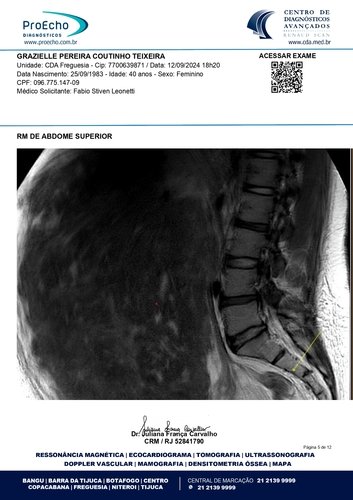

Olá, meu nome é Grazielle, tenho 41 anos e estou enfrentando a batalha mais difícil da minha vida. Fui diagnosticada com quatro miomas, sendo que o maior deles mede 30 x 20 x 28 cm e está comprimindo meus órgãos internos, além de endometriose, um cisto no ovário direito, mucocele de apêndice e um nódulo no intestino. Minha barriga está tão inchada que parece a de uma mulher grávida de 9 meses. Mas, apesar da aparência, o que mais preocupa os médicos é o apêndice inflamado. Se ele estourar, pode causar uma infecção generalizada e me levar a óbito. O tempo é curto: os médicos recomendaram que eu faça a cirurgia no máximo em três meses.

Abaixo, você encontrará os laudos médicos e imagens dos exames que comprovam o meu diagnóstico, bem como o orçamento detalhado da cirurgia. Se tiver alguma dúvida, estarei à disposição para fornecer mais informações.

Ressonância magnética: https://drive.google.com/file/d/1oSvors6sJRCRTZHVSZs9YeKzpw54SFw5/view?usp=sharing